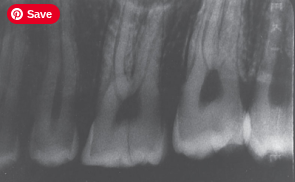

Overlapping Contacts

What it looks like:

Teeth appear stacked on top of each other and you can’t see between them.

Cause:

Incorrect horizontal angulation.

Fix:

Direct the beam through the contact points.